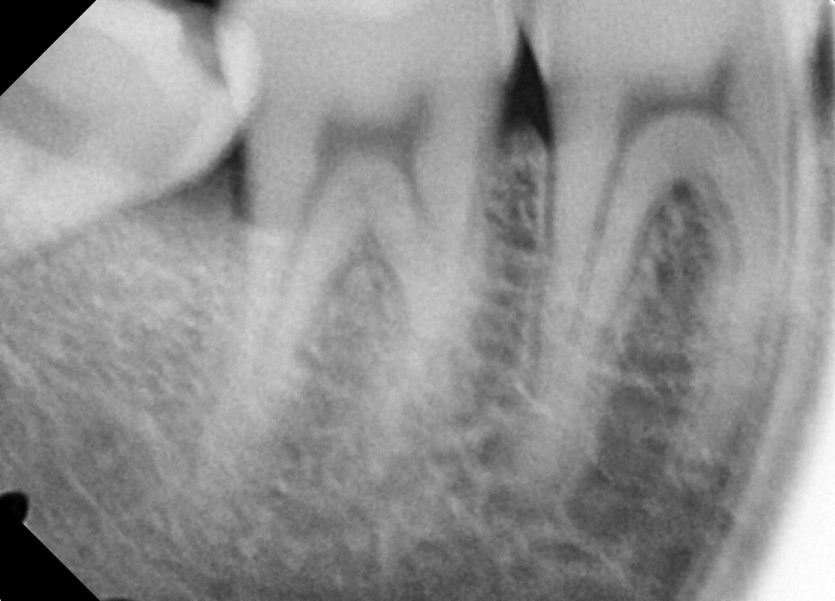

#18,48 사랑니 발치

구강 외과 전문의가 당일 발치했습니다.